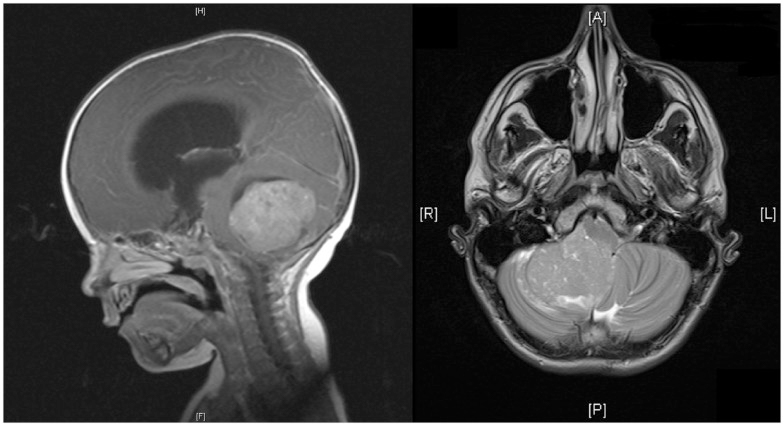

Medulloblastomas

Medulloblastomas are common tumors in childhood, often presenting with vomiting and headache. These tumors are located in midline of the cerebellum (back of the head). Diagnosis is made with MRI, and complete excision can be done safely in majority of the children.